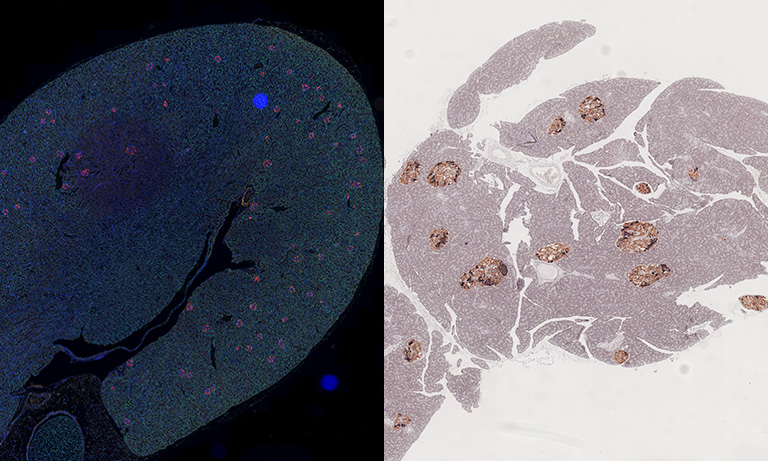

In addition to brightfield images, the NanoZoomer S60v2 Digital slide scanner can also handle fluorescence-stained specimens with the addition of a fluorescence imaging module (optional).

Having both brightfield and fluorescence WSI capabilities enables high-resolution digitization for spatial analysis, multiplex biomarker detection, and quantitative tissue profiling.

A high-sensitivity CMOS camera dedicated to fluorescence enables fast fluorescence WSI imaging.

Courtesy of Yo Shinoda PhD, Teiichi Furuichi PhD, Laboratory for Molecular Neurogenesis, Riken Brain Science Institute